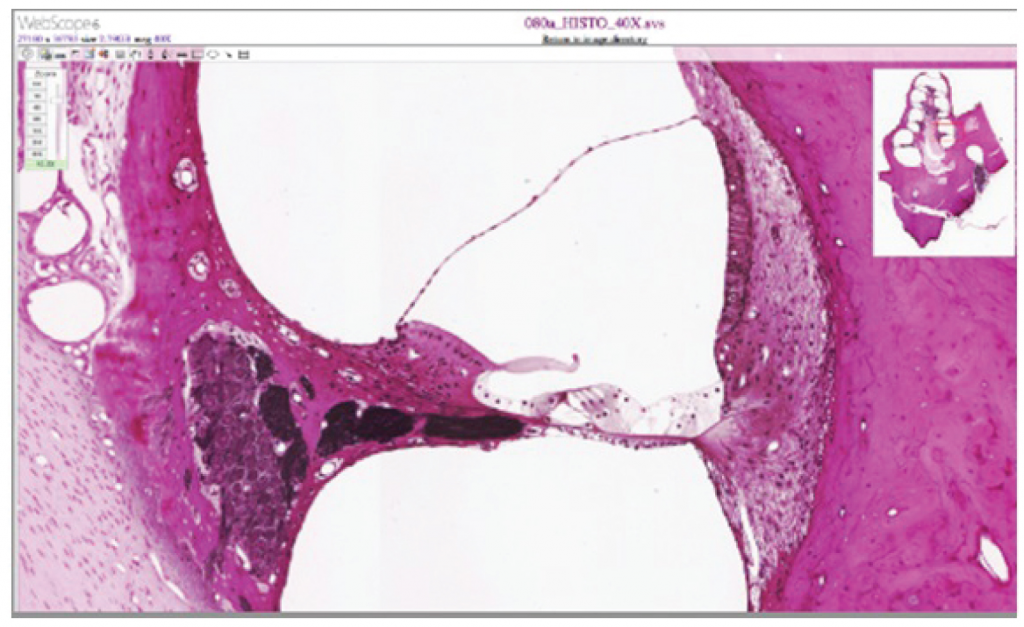

Cochlea and organ of corti.

Figure 13.10.8. Cochlea and organ of corti. LM × 412. (Micrograph provided by the Regents of University of Michigan Medical School © 2012).